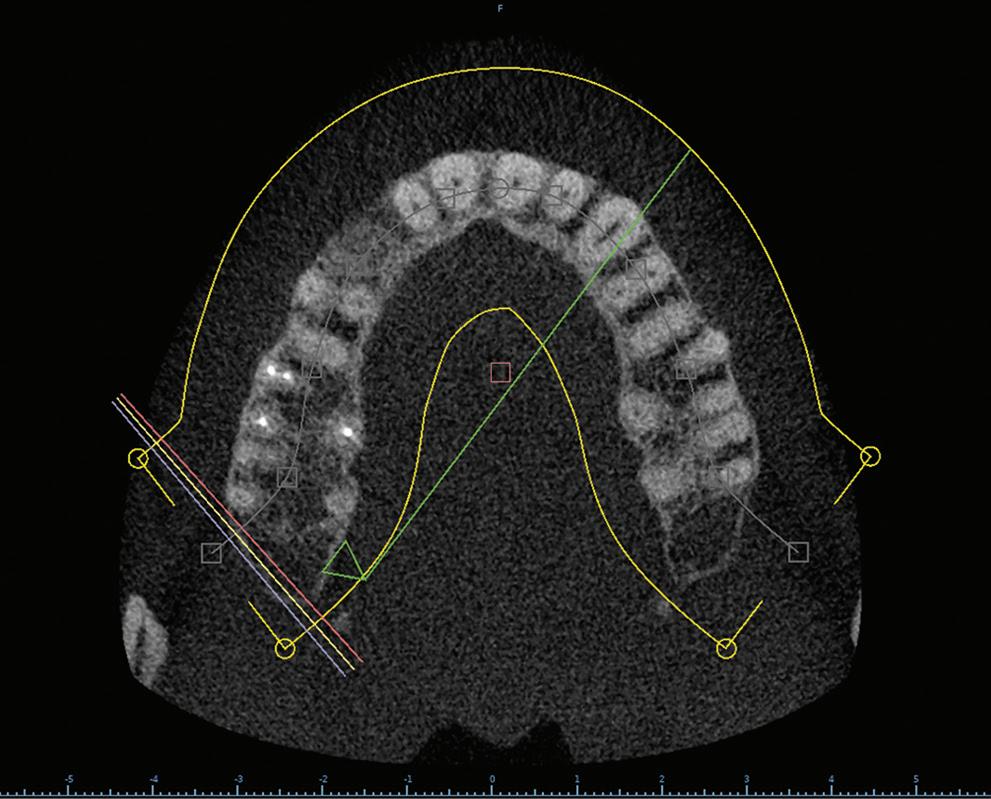

After tooth extraction and socket preservation, patients heal for at least 3 to 4 months. Once the healing process is complete, among the most important procedures for implant planning are cone beam computed tomographic (CBCT) and intraoral scans. The CBCT scan is a 3-dimensional (3D) radiograph that shows the patient’s bone in ways that cannot be seen on 2-dimensional images such as periapical, bitewing, or panoramic radiographs. The use of CBCT scans for implant cases is becoming common because of the important information provided, including bone height, bone width, and the location of arteries, veins, nerves, and other important anatomical features.2

In addition, CBCT images can be used to assess bone density. Bone density ranges from D1 to D4.3 The density is measured in a ratio of cortical-to-cancellous bone. Cortical bone, which makes

up the outer portion of the bone, is dense and has low vascularity. Cancellous bone, which makes up the inner portion of the bone, is not dense and has higher vascularity. D1 bone consists of a high percentage of highly dense cortical bone and minimal to no cancellous bone. D4 bone has a high percentage of low-density cancellous bone and little to no cortical bone. In bone that is more cortical and more dense, the clinician will generally make a larger osteotomy to reduce the stress put on the dense bone. In bone that is less dense and more trabecular, the clinician can make a more undersized osteotomy to ensure good primary stability of the implant. Depending on the type and density of bone found on the preoperative CBCT, the clinician can modify the implant placement technique to adjust for the findings. In my experience, the density of grafted sites is usually classified as D2, but this can vary depending on the type of graft used (Fig 1 and 2).

Fig 1. CBCT images confirm healing of the extraction site after grafting. Fig 2. An occlusal CBCT view reveals the density of the healed graft.

Fig 3. CBCT images of the proposed implant at the site. The digital wax-up can be seen outlined in blue. Placing the implant in a biologically sound position yields a restoration with facial screw access, making a screw-retained restoration an unesthetic option.